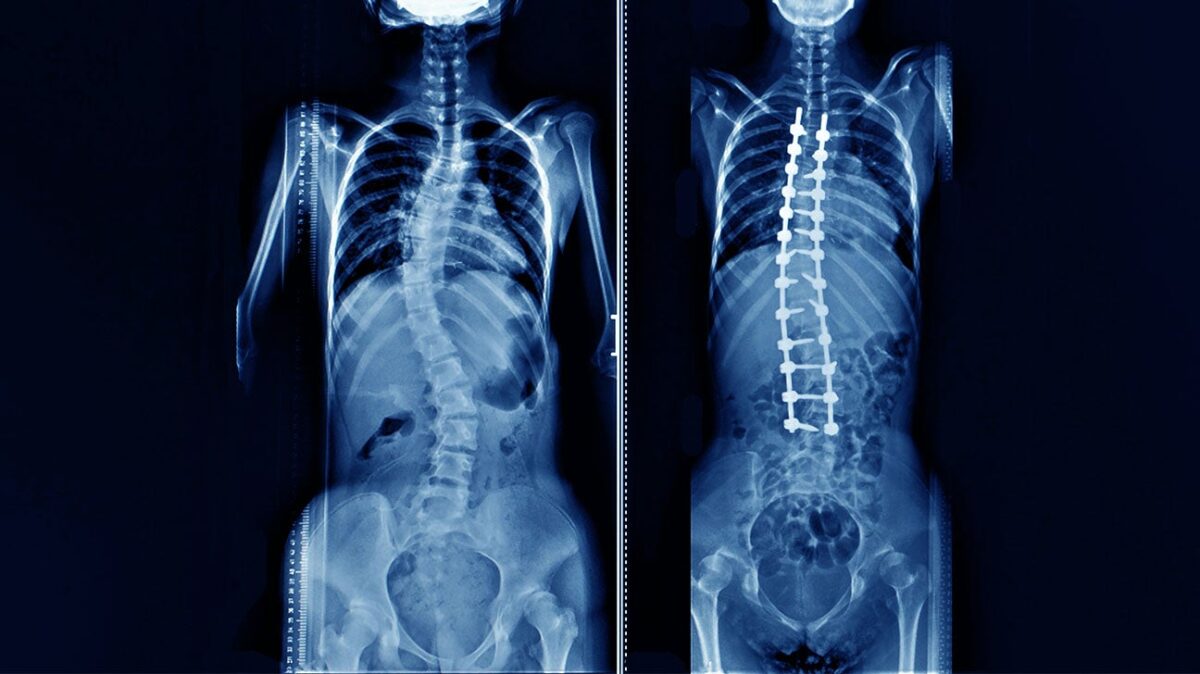

جوشخوردگی ستون فقرات (Spinal Fusion) یکی از رایجترین روشهای جراحی برای درمان دردهای مزمن و شدید پشت است، که در آن دو یا چند مهره به هم متصل میشوند. این عمل درصد شکست به نسبت بالایی دارد. درمانهای فعلی اغلب وابسته به پیوند استخوان یا فاکتورهای رشد قوی هستند، که میتوانند باعث عوارضی مانند رشد غیرقابل کنترل استخوان در نواحی ناخواسته شوند.

فناوری جدید شرکت Bone Biologics مبتنی بر یک پروتئین اختصاصی به نام rhNELL-1 است. این پروتئین به طور طبیعی در رشد استخوان نقش دارد. نتایج مطالعات نشان دادهاند که پروتئین NELL-1 قادر است به صورت هدفمند و دقیق، رشد استخوان را در محل مورد نظر تحریک کند و همزمان از ایجاد سلولهای چربی جلوگیری نماید، که یکی از مشکلات شایع در درمانهای مشابه است.

این عملکرد دوگانه، میتواند باعث موفقیت بیشتر در جوشخوردگی مهرهها و کاهش عوارض جانبی درمان شود.